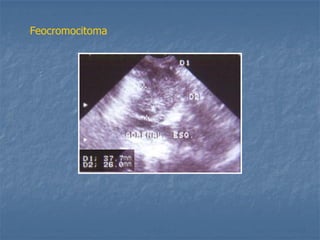

Feocromocitoma

 Hiperadrenocorticismo - Neoplásico: *massa unilateral, ecotextura heterogênea e atrofia contra lateral * pode haver presença de massas adrenais não funcionantes e ausência de atrofia contra-lateral * pode haver massa adrenal bilateral * pode haver pouca atrofia contra-lateral * pode haver presença de trombos metastáticos na V.C.C.